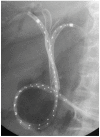

Malignant hilar biliary obstruction (HBO) represents a complex clinical condition in terms of diagnosis, surgical and medical treatment, endoscopic approach, and palliation. The main etiology of malignant HBO is hilar cholangiocarcinoma that is considered an aggressive biliary tract's cancer and has still today a poor prognosis. Endoscopy plays a crucial role in malignant HBO from the diagnosis to the palliation. This technique allows the collection of cytological or histological samples, direct visualization of the suspect malignant tissue, and an echoendoscopic evaluation of the primary tumor and its locoregional staging. Because obstructive jaundice is the most common clinical presentation of malignant HBO, endoscopic biliary drainage, when indicated, is the preferred treatment over the percutaneous approach. Several endoscopic techniques are today available for both the diagnosis and the treatment of biliary obstruction. The choice among them can differ for each clinical scenario. In fact, a personalized endoscopic approach is mandatory in order to perform the proper procedure in the singular patient.